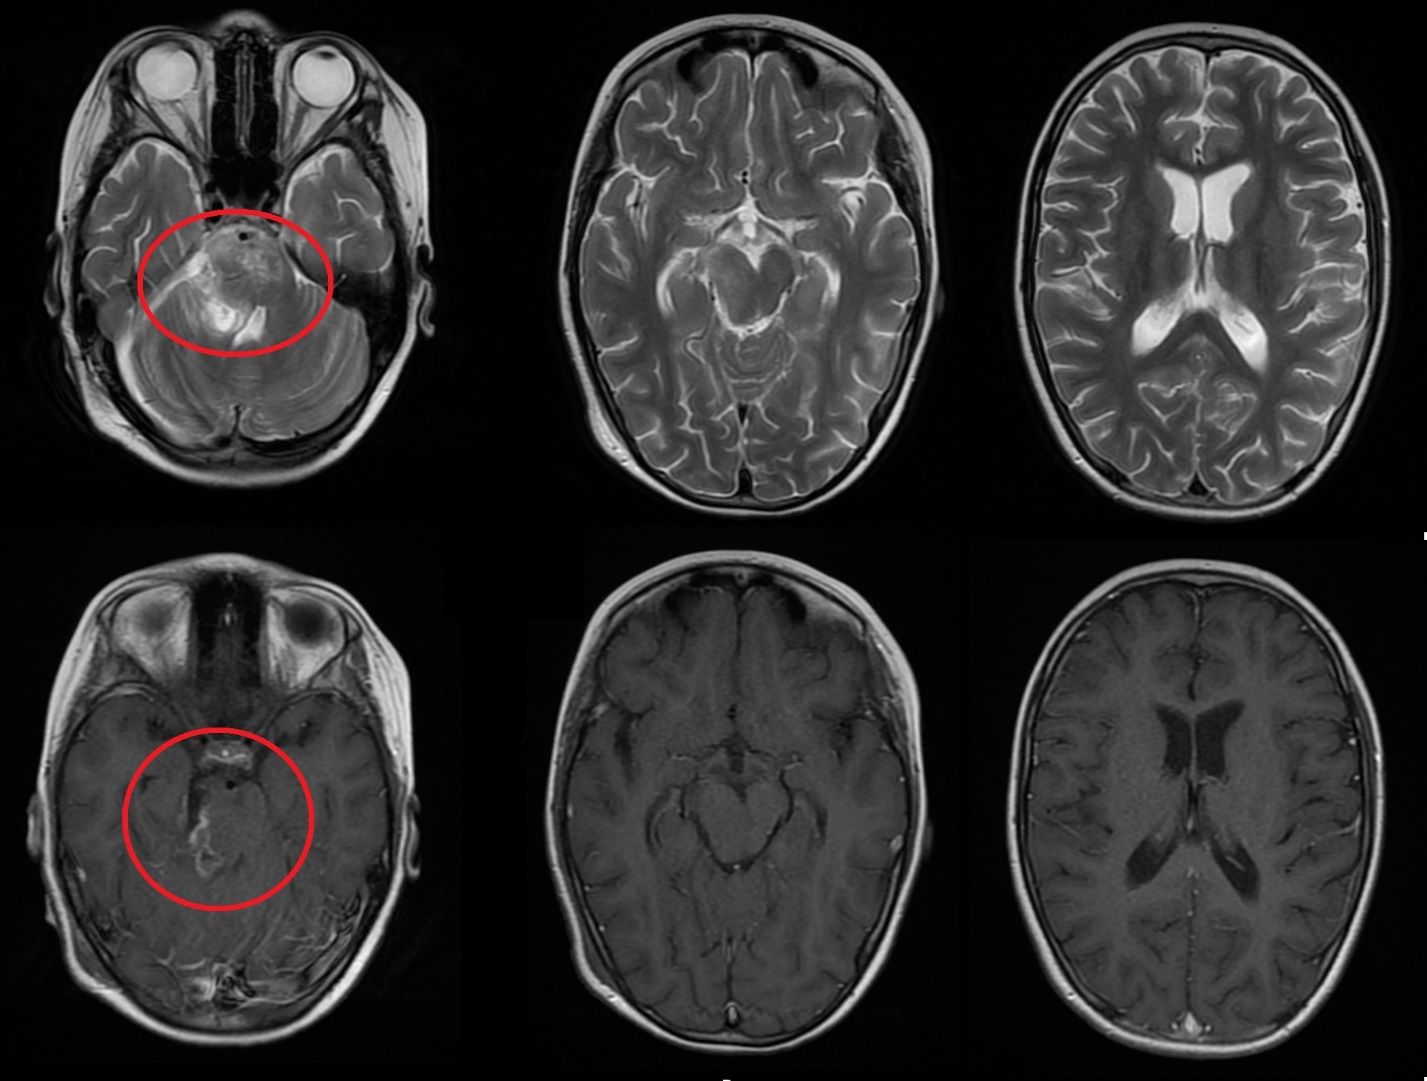

Результаты. У 19 пациентов (50 % от 38 прошедших биопсию) по данным иммуногистохимического анализа послеоперационного материала была выявлена мутация К27М в гене H3F3A. У 6 (15 %) пациентов из 38 МРТ в сроки от 2 до 5 мес (медиана – 4,5 мес) после окончания лучевой терапии выявлено нехарактерное прогрессирование ДСГ в виде метастазирования по желудочковой системе головного мозга. У остальных пациентов когорты исследования, не проходивших процедуру биопсии, подобный характер прогрессирования не наблюдался (p<0,002): у них, как правило, отмечался продолженный рост опухоли (n=96), у 4 больных диагностировано лептоменингеальное метастазирование по спинному мозгу.

Заключение. Нами выявлены случаи нетипичного прогрессирования ДСГ в виде метастазирования по желудочковой системе у детей после открытой биопсии опухоли. Есть основания полагать, что биопсия могла способствовать диссеминации ДСГ по ликворным пространствам. Необходим поиск альтернативных методов оценки молекулярно-генетических характеристик ДСГ.